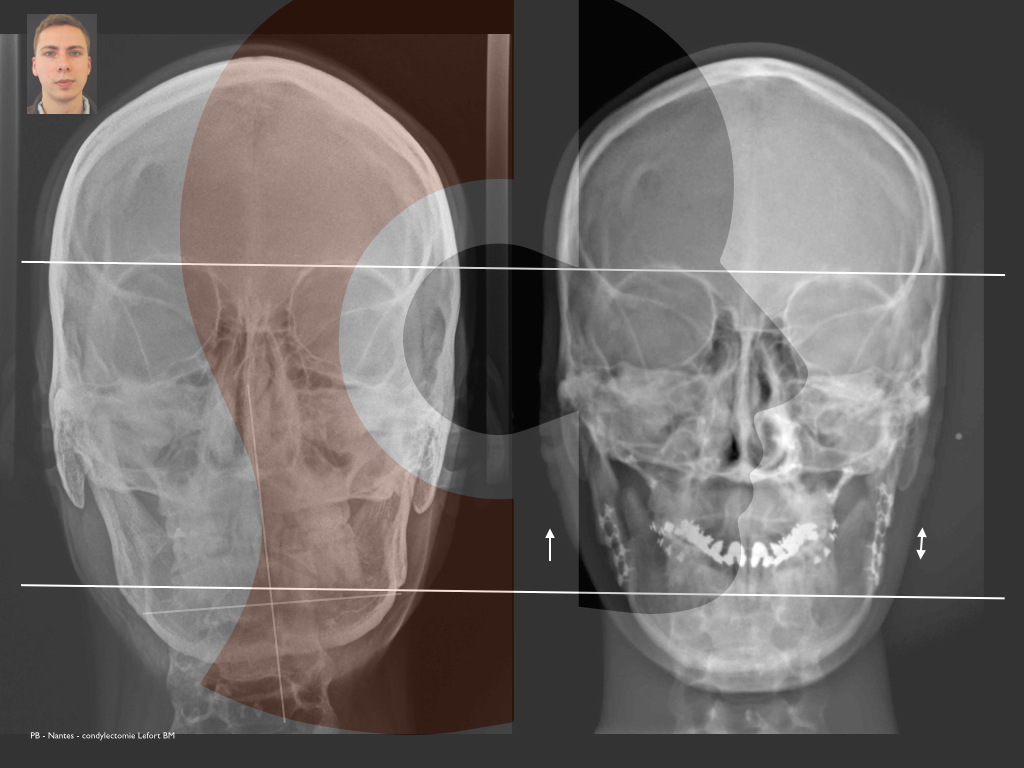

Hypercondylie droite opérée par une condylectomie par un abord externe, associée à un abaissement de l’angle mandibulaire Gche, remontée de l’angle mandibulaire droit, et une horizontalisation du maxillaire